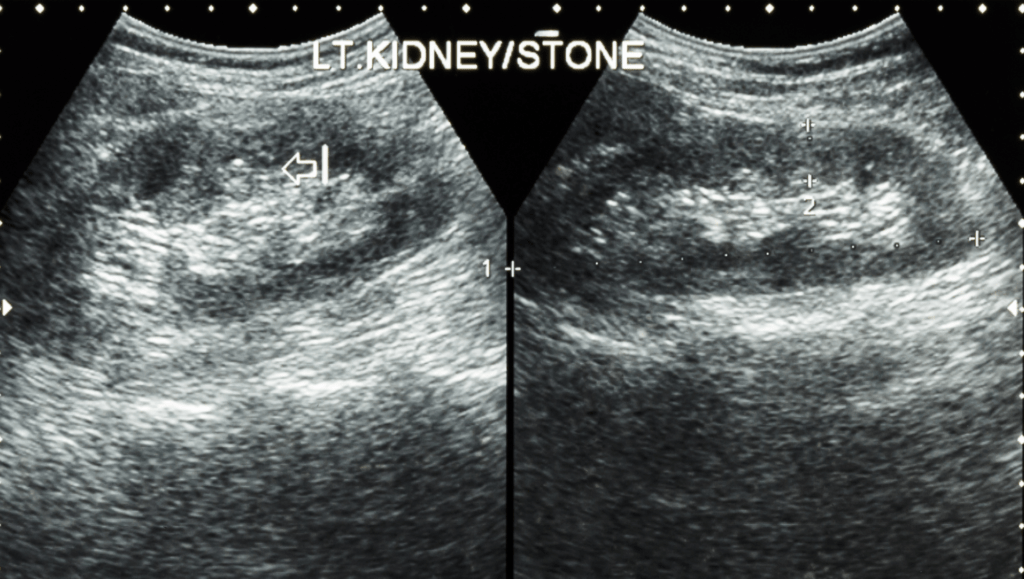

- układu moczowego (nerek, moczowodów, pęcherza moczowego, gruczołu krokowego),